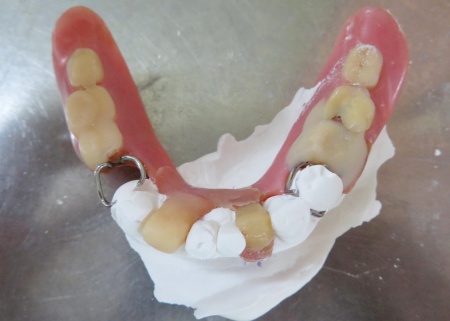

| カウンセリング・診断結果 | 拝見したところ、左下の歯には部分入れ歯が装着されていましたが、入れ歯を支える金属バネ「クラスプ」が破損しており、入れ歯をしっかりと固定することができなくなっていました。 クラスプが折れた状態では入れ歯が安定せず、食事中などに外れやすくなります。 また、破損した入れ歯を使い続けると、入れ歯が歯茎にこすれて傷が付いたり、顎の関節や残っている歯に過度な負担がかかったりするリスクがあります。 以上のことから、折れたクラスプを作り直す必要があると診断しました。 |

| 行ったご提案・治療内容 | 今回は、破損していたクラスプを新しく作り直し、入れ歯を修理する方法を提案しました。 これまでも同様の修理を行っているため、患者さまも修理の流れをよく理解されています。 入れ歯を修理する場合は、入れ歯をお預かりして数日から1週間ほどお時間をいただくのが一般的ですが、当院では歯科医師が院内でクラスプを作製できるため、約1時間で修理をすることが可能です。 ただ長期的な使用状況によっては、再度調整や修理が必要になることもあります。 修理方法のメリットとデメリットをお伝えし、同意いただきました。 まずは入れ歯を装着した状態で型取りを行い、模型を作製します。 完成した模型に入れ歯を装着し、クラスプを固定する場所を削りました。 クラスプ用のワイヤーは手作業で曲げながら、残っている歯の形態や傾きに合わせて精密に調整します。 その後、完成したクラスプを入れ歯に取り付けたうえで装着していただき、実際にお口の中で安定性や装着感を確認しました。 最後に、噛み合わせや着脱のしやすさ、見た目に問題がないかなどを確認し、治療を終了しています。 |

クラスプを固定する場所を削りました

外側のクラスプの位置を確認しました

内側のクラスプの位置を確認しました